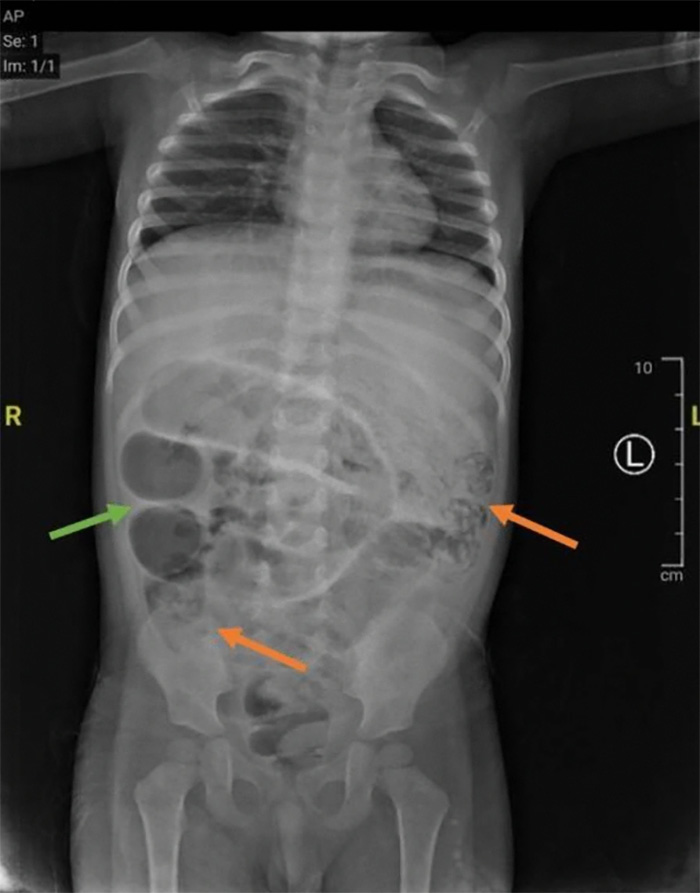

ผลการตรวจเลือดแสดงให้เห็นว่า เด็กมีภาวะโลหิตจางและเม็ดเลือดขาวสูง ขณะที่ผลการเอกซเรย์ช่องท้อง แสดงให้เห็นการอุดตันในลำไส้ของเด็กชาย ทีมแพทย์จึงต้องใช้วิธีการผ่าตัดในการรักษา